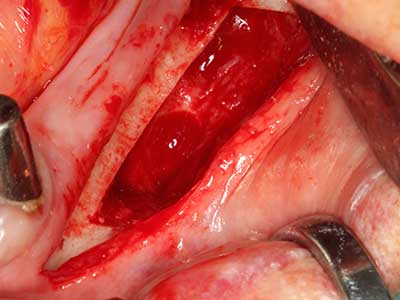

Bei der Knochenblockentnahme zeigen sich weitere Vorteile für die Piezochirurgie: Neben der bereits beschriebenen hohen Präzision bei der Osteotomie stellt sich gerade die Verwendung der dünnen Sägespitzen als besonders materialschonend heraus. Bei der Verwendung insbesondere von Lindemannfräsen sind mit deutlich höheren Entnahmeverlusten durch die dickere Instrumentenspitze zu rechnen (Lakshmiganthan, Gokulanathan et al. 2012). Die insbesondere bei retromolar entnommenen Blocktransplantaten notwendige basale Abtrennung wird durch speziell hierfür vorgesehene rechtwinklige Sägen erleichtert, so dass die Piezochirurgie als präzises, übersichtliches und sicheres Verfahren zur retromolaren Knochenblockgewinnung angesehen wird (Happe 2007) (Abb. 1-12).

Sollen chirurgische Eingriffe mit unmittelbarer Knochenbeziehung an empfindlichen Strukturen wie Blutgefäßen oder Nerven erfolgen, so bergen rotierende Instrumente ein erhebliches Potential an iatrogener Schädigung. Gerade bei Nervdarstellungen nach iatrogener Schädigung, oder aber im Zuge einer Nervlateralisation für resektive und rekonstruktive Eingriffe oder Implantatinsertionen können piezoelektronische Geräte hilfreich sein Knochendeckel zu präparieren und nervnahe Hartgewebsanteile zu entfernen (Abb. 17-20). Ein leichter Kontakt des Nervstrangs zur Piezospitze bleibt dabei in der Regel folgenlos – allerdings kann eine unvorsichtige Vorgehensweise mit sägeartigen Bewegungen bzw. Ansätzen bei noch vorhandener knöcherner Unterlage durchaus temporäre oder aber auch permanente Nervschädigungen verursachen. Das Risiko einer solchen Schädigung wird jedoch als wesentliche geringer eingeschätzt als unter Anwendung von Säge- oder Fräsinstrumenten (Pereira, Gealh et al. 2014).